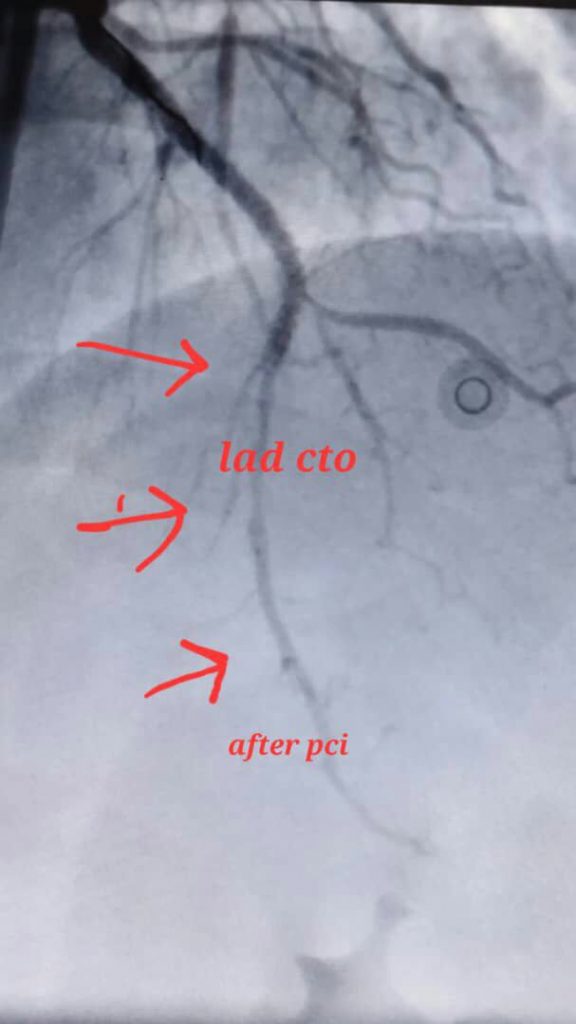

آنژیوپلاستی عروق تنگ یا کاملا مسدود قبلی , والووپلاستی

درمان انسداد کامل عروق قلبی بدون نیاز به عمل جراحی باز